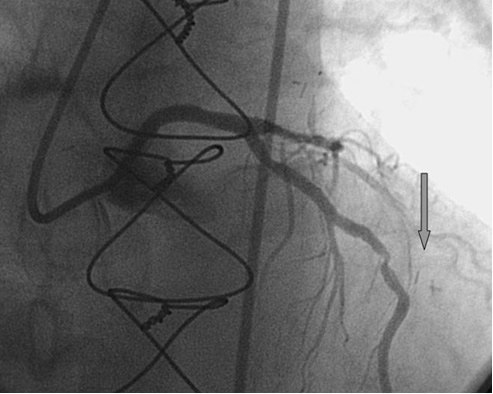

PCI of the vein and arterial grafts have unique challenges. For any PCI, guide support is very important for successful balloon and stent delivery. In a tortuous vein graft with a steep angle, advancement of a stent can be very difficult and challenging. Therefore, it is important to choose the best available catheter before starting PCI. Similar to the right coronary angiography, a JR4 guide catheter is most commonly used in this setting. However, Amplatz guide catheters for left vein grafts and multipurpose catheters for right vein grafts are better choices in certain anatomy. In Figure 8 and Figure 10 two examples of poor guide support in two vein graft interventions can be seen. Initially, a JR4 guide was used for PCI of the vein graft supplying the left anterior descending artery (LAD) without any success. However, after changing the guide to an Amplatz left 2 guide catheter, we achieved excellent support without any difficulty in advancing two stents (Figure 9). In Figure 10, difficulty is illustrated in engaging the vein graft ostium supplying the right coronary artery with a JR4 catheter. This vein graft has a very steep inferior take off from the aorta. After changing the guide to a multipurpose catheter, we were able to deliver three stents successfully without any difficulties (Figure 11). Similar challenges exist in the treatment of the left IMA or right IMA. These arterial grafts can be extremely tortuous making stent delivery very difficult. It may be necessary to use short length stents for a better deliverability or stents with lowest profile. Usually, similar to the native coronary intervention, a 6 French guide is appropriate for the routine use.

The most commonly used catheters for left heart catheterization and vein graft angiography can be seen in Figure 1 and Figure 4-13. Most of the vein grafts have horizontal take off and can be successfully engaged using a commonly used Judkins right number 4 (JR4) catheter. The JR4 catheter is the most commonly used catheter for the engagement of the right coronary ostium with horizontal take off. However, many vein grafts have unusual take off requiring different catheters. Many right coronary vein grafts have steep inferior take off making the ostial engagement with JR4 difficult or impossible (Figure 10). In such a scenario, a multipurpose catheter which has a shallow angulation is the best choice (Figure 11). The second major challenge in engaging vein graft ostia, particularly vein grafts supplying the left coronary arteries, is the shape of the aorta. A large aorta can make it very difficult for the JR4 catheter to reach the ostial vein grafts. In such a situation, Amplatz (AR) right and left (AL) catheters can be very helpful to reach the vein graft ostia. Amplatz catheters have a larger primary curve and have been used successfully in unusual superior take off of left coronary arteries or vein grafts and in large aorta. Amplatz catheters are available in different sizes (from smaller to larger curve: AR 1, AR2, AL2, AL2 and AL3). Occasionally, a very superior take off of a vein graft requires specially designed bypass graft catheters. Amplatz catheters are also extremely helpful in engaging native right coronary ostium with anterior take off.